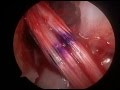

Acl Reconstruction surgery Hamstring Graft Animation

Anterior cruciate ligament (acl) reconstruction. · dr. Bertram zarins at mass general hospital has prepared this animation to explain how he reconstructs a torn acl with a mid3rd patellar tendon graft.